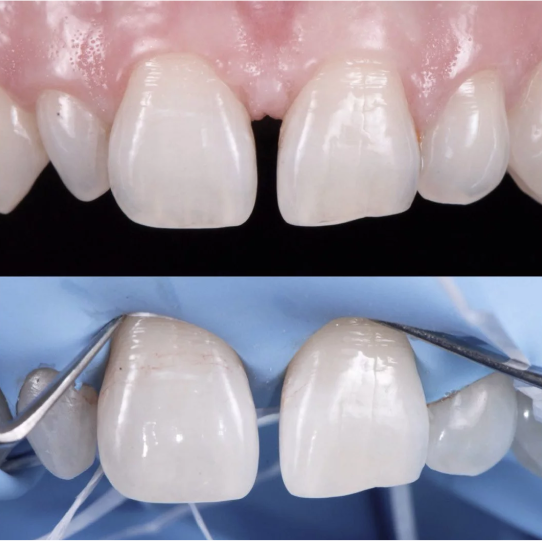

Leczenie kanałowe w praktyce – Jak to wygląda w naszym gabinecie?

W naszym gabinecie każde leczenie kanałowe w praktyce jest przeprowadzane z użyciem mikroskopu zabiegowego. Dla nas to podstawa precyzyjnego i bezpiecznego leczenia endodontycznego. Mikroskop pozwala nam precyzyjnie uzyskać dostęp do kanałów korzeniowych przy minimalnej destrukcji zdrowych tkanek samego zęba. Widzimy więcej, więc leczymy dokładniej. Zawsze stosujemy ślinochron (koferdam), aby zapewnić sterylność i bezpieczeństwo podczas zabiegu. Używamy również nowoczesnych narzędzi maszynowych, wykonanych ze specjalnych stopów (np. NiTi), które są elastyczne i minimalizują ryzyko złamania narzędzia w kanale, nawet w przypadku zakrzywionych kanałów.

Leczenie kanałowe pod mikroskopem to złoty standard współczesnej stomatologii zachowawczej i endodoncji. Jest to metoda, która w naszym gabinecie jest standardem, zapewniając bezbolesne leczenie kanałowe na najwyższym poziomie. Używamy mikroskopu endodontycznego oraz koferdamu.